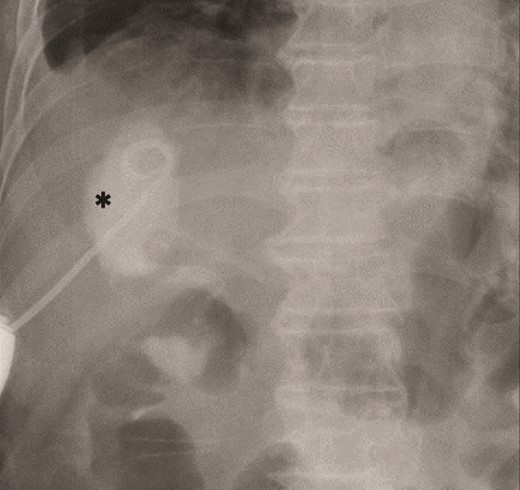

The amylase levels of drainage fluid and blood at postoperative day (POD) 1 (Ascites 6980 IU/dl, Serum 1123 IU/dl) and POD 3 (Ascites 673 IU/dl, Serum 487 IU/dl) revealed pancreatic fistula based on the criteria of International Study Group of Pancreatic Fistula [2]. After that, their results improved, and fluoroscopy showed no stenosis and leakage. Therefore, we removed all drains at POD 8, however the following day, the patient developed high fever. Plain CT revealed intraperitoneal fluid around subdiaphragmatic and duodenal stump (Fig. 3). We inserted a pig-tail drainage tube to the subdiaphragmatic space (Fig. 4). Since biliary fluid was discharged through the tube, we suspected duodenal leakage and started infusion of somatostatin analogs and antibiotics. At POD 13, the patient complained of whole abdominal pain with peritoneal signs. As the patient became hemodynamically unstable, we performed emergent laparotomy to lavage and insert multiple drainage tubes. Two perforation pinholes were identified in the anterior wall of the duodenum, near the stump. We resected the vulnerable duodenal stump including the perforation site and closed by Gambee’s method with unabsorbable 4–0 proline (Fig. 5). We inserted multiple drainage tubes (Fig. 6a): a C-tube from the cystic duct into the common bile duct to separate biliary juice and pancreatic juice, a dual drainage tube around the duodenal stump with continuous suction (Fig. 6b), a simple intraluminal drainage tube via the duodenum near the stump through a new skin incision on the left side of the abdomen for duodenal decompression, and a drainage tube into the rectovesical pouch. After the reoperation, we irrigated the cavity around the duodenal stump through each drain with saline. Since the contrast agent did not flow into the duodenum and the cavity around the duodenal stump gradually got smaller (Fig. 7), oral intake of fluid diet was initiated at POD 37. However, fistulography at POD 44 showed that the fistula of duodenal stump had relapsed (Fig. 8). Although we considered performing second reoperation for duodenal stump closure, due to the cavity around the duodenal stump was located, we continued conservative management and irrigation via drainage tubes. Fistulography demonstrated no leakage from the duodenal stump at POD 56, and the patient discharged at POD 59.

Diagnosis of postoperative duodenal perforation. CT showed ascites in subdiaphragmatic space (arrow) and around duodenal stump (circle) at POD 8.